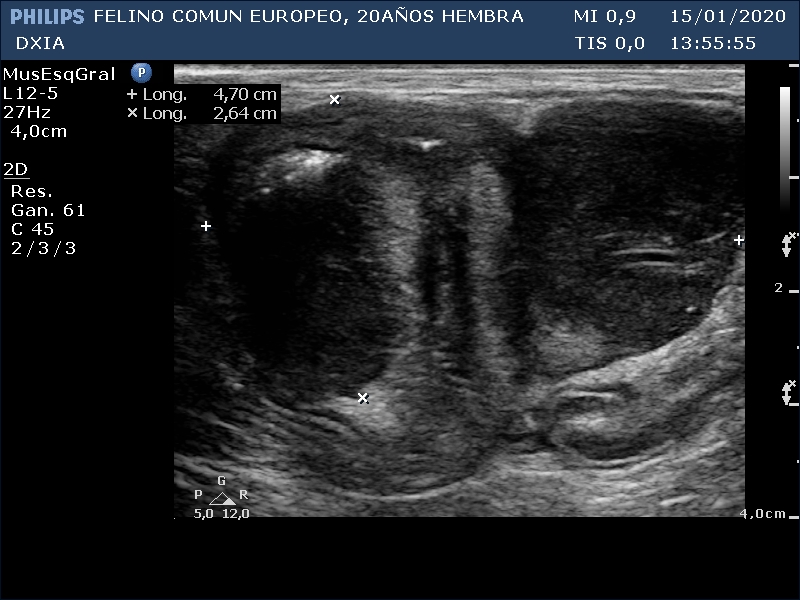

FRANGELICA

Gato común europeo, hembra, de 20 años.

Con pérdida de peso y analíticas realizadas sin presencia de alteraciones. Su veterinario a la palpación detecta una masa abdominal

Se realiza ecografía y se observa alteración compatible con neoformación en asa del intestino delgado.

Asa del ID con aumento de grosor de su pared, pérdida de estructura en capas. Neoformación hipoecogénica.

Ganglio yeyunal con aspecto globoso, hipoecogénico y bastante homogéneo, índice mayor de 0.5. Compatible con mayor probabilidad con proceso tumoral o metastásico.

Lóbulos hepáticos con bordes afilados y parénquima homogéneo. Se observa presencia de líquido libre anecogénico entre dichos lóbulos.

Asa del ID con neoformación sin definición de capas intestinales.